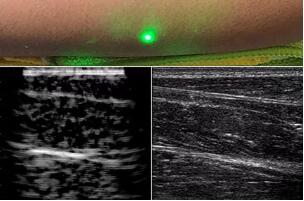

目前,研究人員已經(jīng)與健康的志愿者測試了他們的系統(tǒng):從半米遠處掃描了他們的前臂,并將這些結(jié)果與傳統(tǒng)超聲的結(jié)果進行了比較。他們能夠觀察到深達6厘米的組織,并能看到肌肉,脂肪和骨頭,并報告其結(jié)果可與標(biāo)準(zhǔn)超聲相媲美。

研究人員用一種激光裝置測試了這個想法,該裝置使用一個波長為1,550納米的脈沖激光來產(chǎn)生聲波,并使用第二個連續(xù)激光,調(diào)諧到相同的波長以遠程檢測反射的聲波。第二個激光器是靈敏的運動檢測器,可測量聲波從肌肉,脂肪和其他組織反射回來而引起的皮膚表面振動。反射的聲波產(chǎn)生的皮膚表面運動會導(dǎo)致激光頻率發(fā)生變化,這種變化可以測量。通過機械掃描人體上的激光,科學(xué)家可以獲取不同位置的數(shù)據(jù)并生成該區(qū)域的圖像。